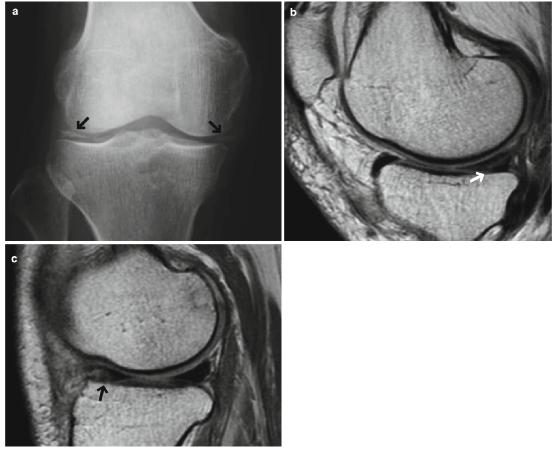

- MRI可能显示代表钙化的半月板内高信号(图7.38)。

图7.38半月板钙化。60多岁的男性。(a)前后位x光片和(b,c ) PDWI。关节间隙可见双侧钙化(箭头a)。MRI显示内侧半月板后段的退化性撕裂(箭头,b)和外侧半月板的前段撕裂(箭头c)